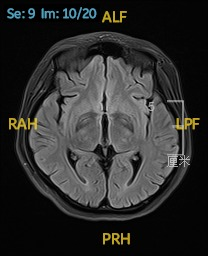

2023.02.24颅脑MR平扫示双侧基底节区及桥脑异常信号,考虑渗透性脱髓鞘综合征,见图3。

图3 2023.02.24颅脑MR成像示双侧基底节区及桥脑见对称性片样长T1长T2信号,FLAIR呈高信号。脑室、脑池、脑沟、脑裂未见明显异常。中线结构居中。